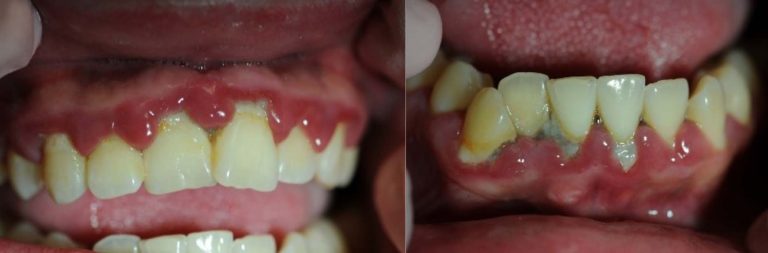

Appendix: Photo- and Radiographs of Periodontal Disease Associated With HIV

Photographs courtesy of Dr. Gwen Cohen Brown and the Dental Hygiene Department of New York City College of Technology

Figure 1: Patient with linear gingival erythema (LGE)

Figure 2: Patient with necrotizing ulcerative periodontitis (NUP)

Figure 3: Patient with linear gingival erythema (LGE) and necrotizing ulcerative periodontitis (NUP)

Figure 4: Patient with necrotizing ulcerative gingivitis (NUG)